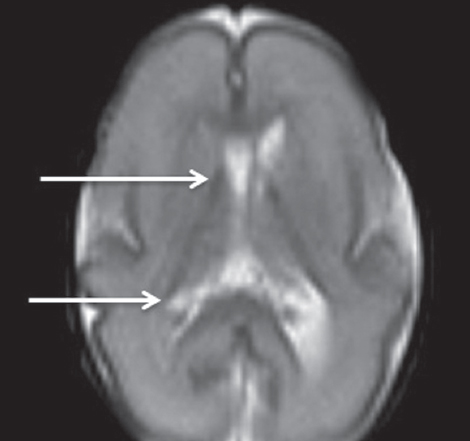

Методы и материал. Выполнено исследование паттерна нейропластичности — регрессии герминального матрикса у недоношенных новорожденных с экстремально низкой массой тела (ЭНМТ) при рождении методами краниальной сонографии (КСГ) и магнитно-резонансной томографии (МРТ). Был обследован 21 недоношенный новорожденный с ЭНМТ без нейровизуализационных признаков повреждения герминального матрикса, в первую очередь кровоизлияния из герминального матрикса. Проведено измерение герминального матрикса передних отделов боковых желудочков головного мозга у исследуемых детей методом КСГ. Выполнено МРТ головного мозга 15 недоношенным детям группы исследования в постконцептуальном возрасте (ПКВ) 27–38 недель с использованием традиционных импульсных последовательностей и дополнительно DWI — диффузионно-взвешенных изображений в стандартных проекциях. Также выполнено патоморфологическое исследование герминального матрикса в области передних отделов боковых желудочков у трех умерших детей из группы исследования.

Результаты и выводы. Выявлена регрессия герминального матрикса у недоношенных новорожденных с полной редукцией к 30 неделям ПКВ по результатам КСГ. Применение DWI ВИ позволило выявить герминальный матрикс у недоношенных детей до 34 недель ПКВ, тогда как при помощи других импульсных последовательностей удается визуализировать герминальный матрикс до 32 недель ПКВ.